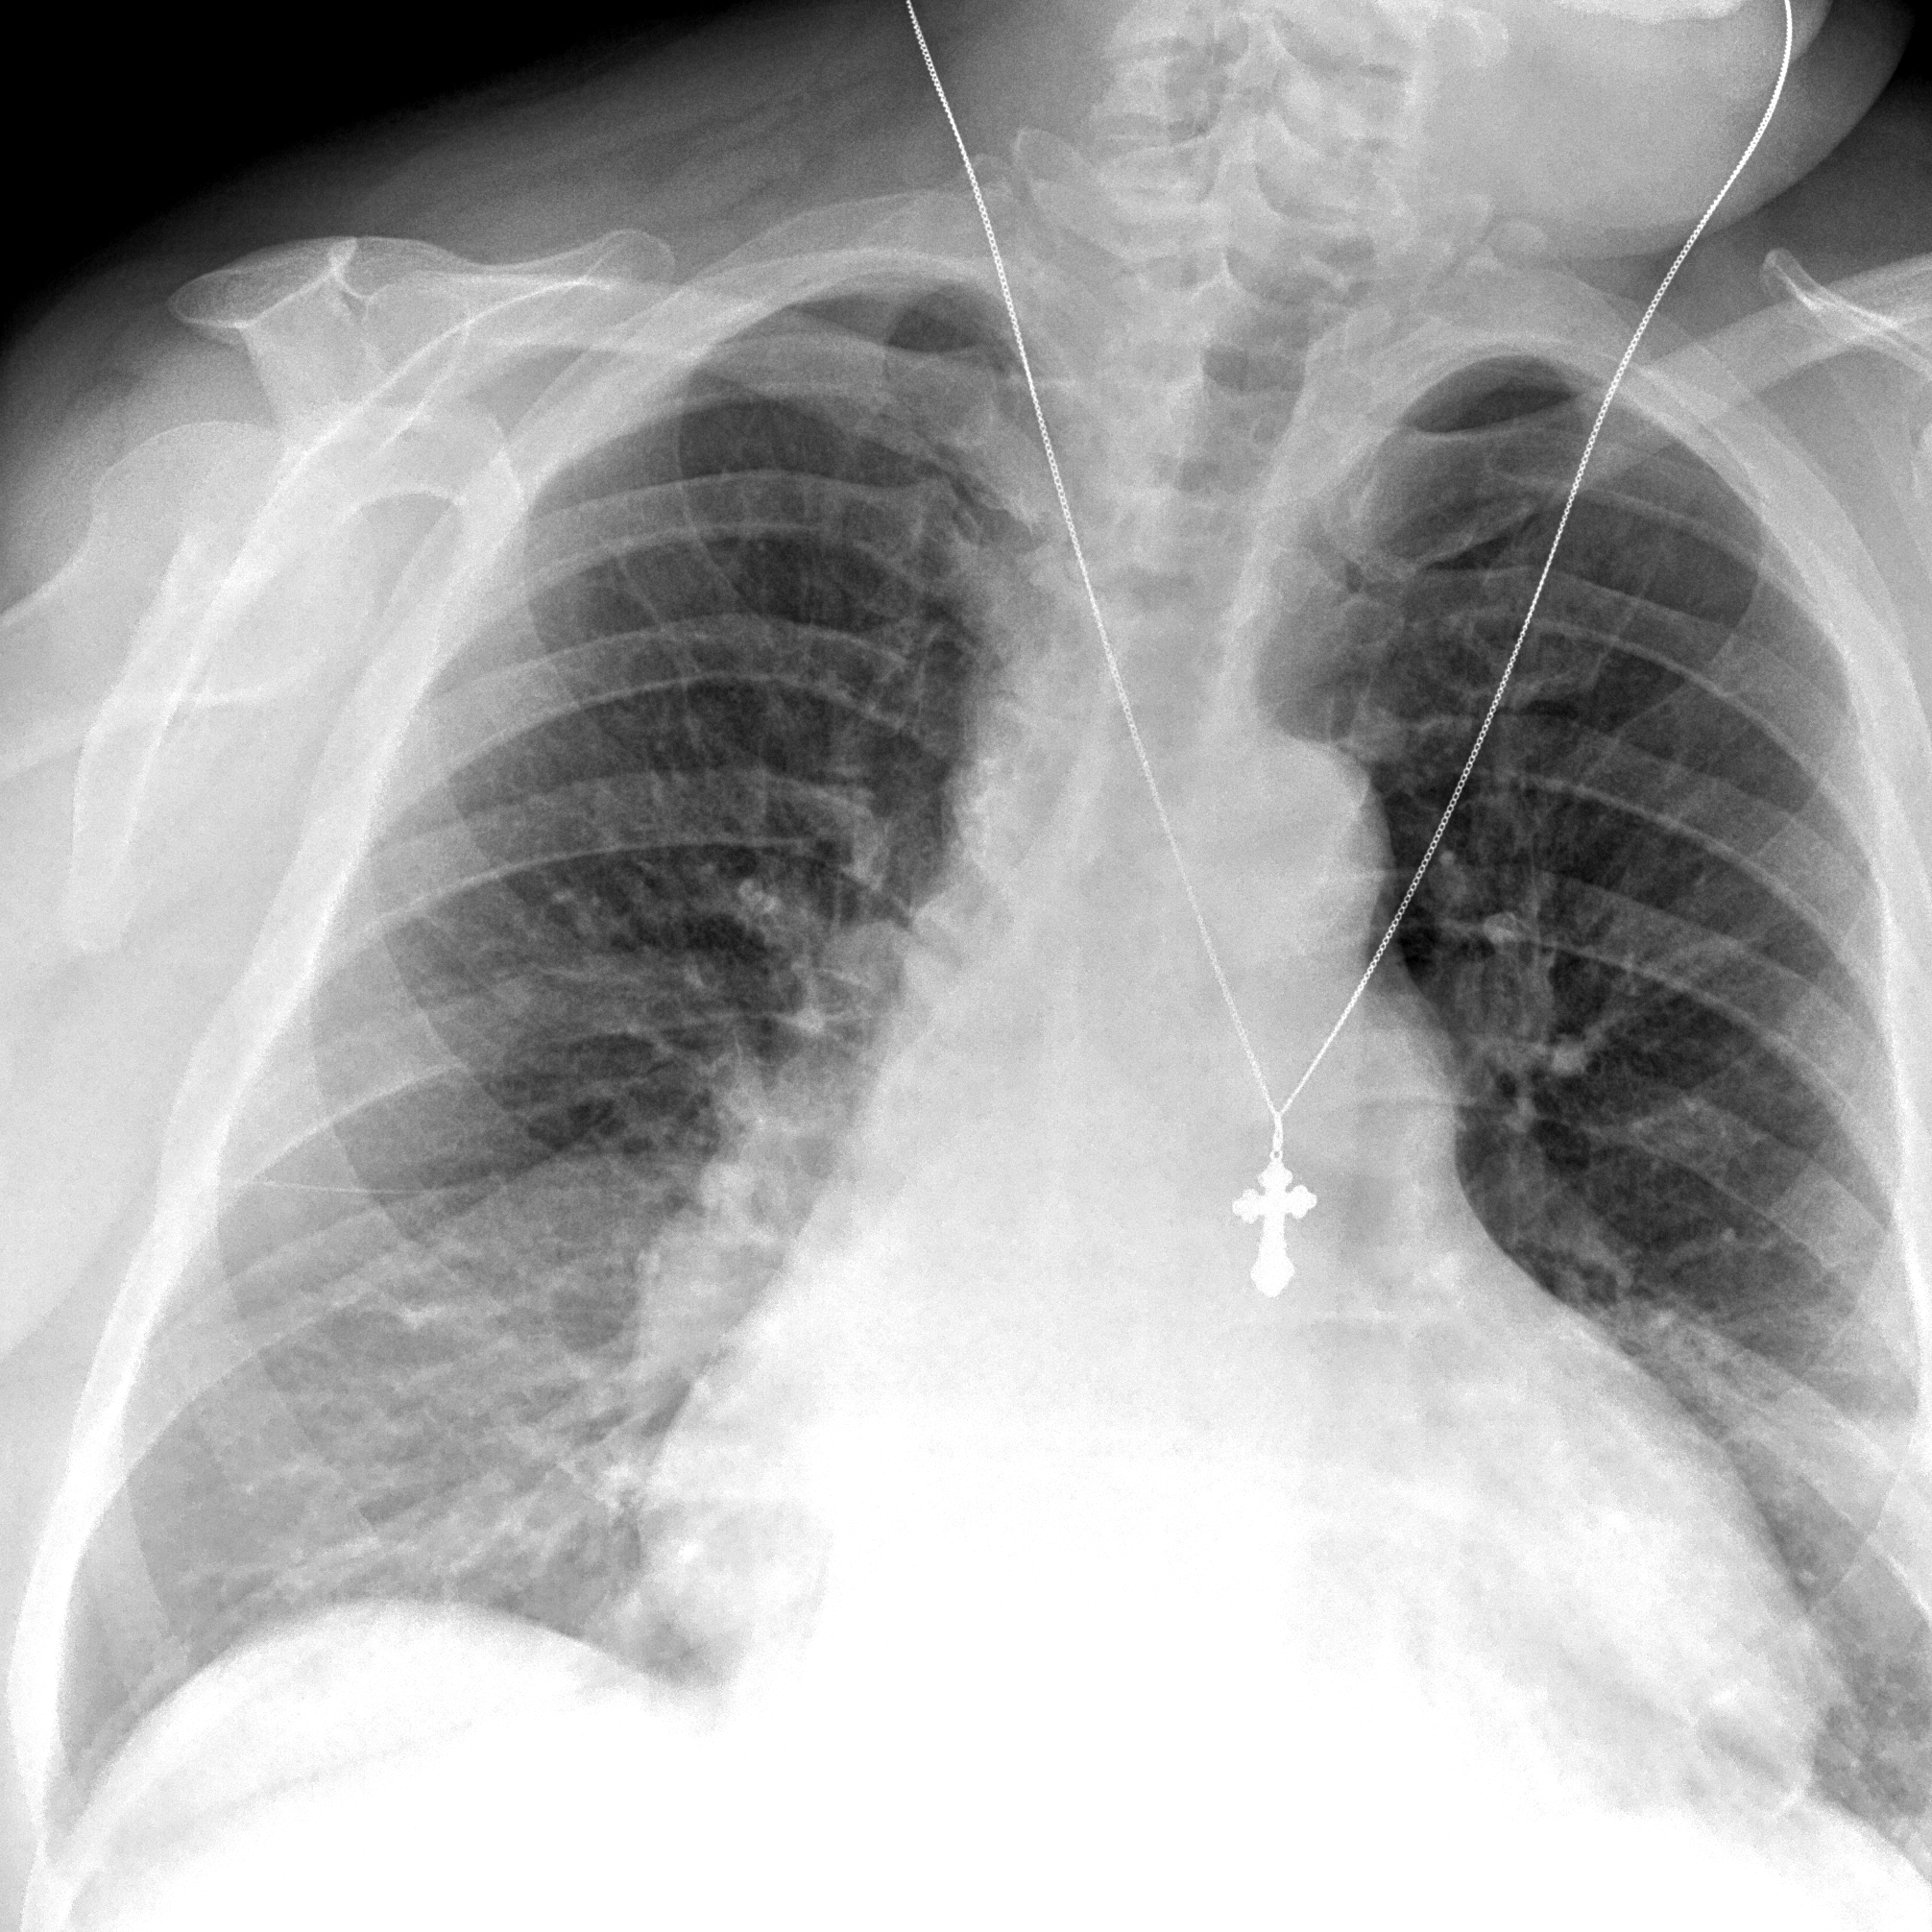

Поражение легких является одним из основных симптомов коронавируса (COVID-19). В данной статье представлены фото рентгеновских снимков, которые позволяют визуально оценить состояние легких при этом заболевании.

Фото рентгеновских снимков поражения легких при COVID-19

На фотографиях рентгеновских снимков видно, как вирус воздействует на легочную ткань. Характерные признаки поражения легких включают пятна, инфильтраты и наличие жидкости внутри легочных альвеол.

Фото рентгеновских снимков помогают врачам и специалистам визуально определить степень поражения легких и принять соответствующие меры лечения и поддержки пациента.